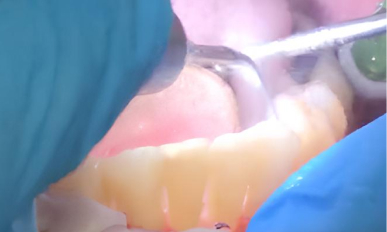

3. Дезинфекция: После лазерной обработки область лечения тщательно промыли антисептическим раствором для удаления остатков бактерий и воспалённых тканей.

Triplo-3.jpg